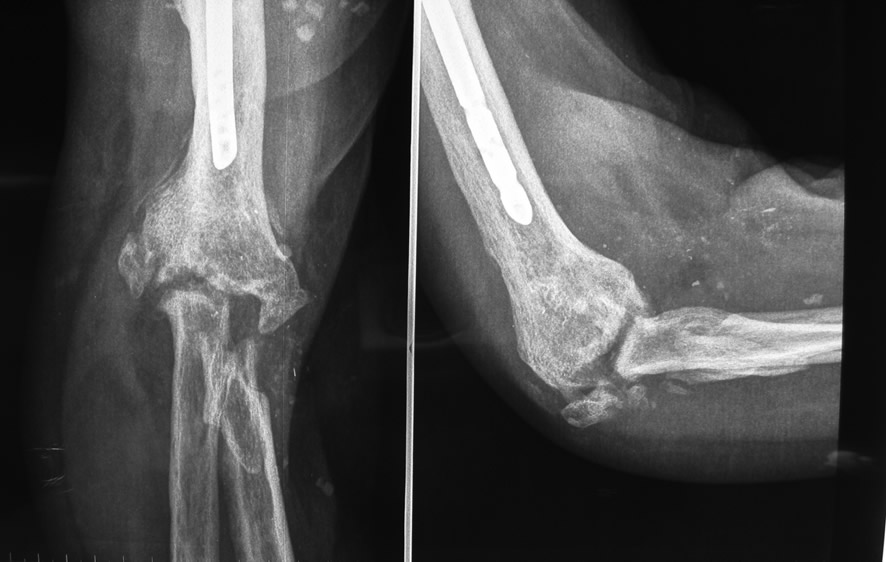

Paciente de 48 años que acude por destrucción de articulación de codo, secuela de fractura múltiplemente operada.

- Múltiples cirugías previas sin éxito

- Poca movilidad de codo

- Dolor articular

Paso 1: Reconstrucción extremo distal de codo con hueso vascularizado

Transferencia de hueso vascularizado de cresta ilíaca tallado a la forma de cúbito proximal.

Paso 2: Reconstrucción de extremo proximal codo con hueso vascularizado

Reconstrucción de húmero distal con transferencia microvascular de peroné tallado.